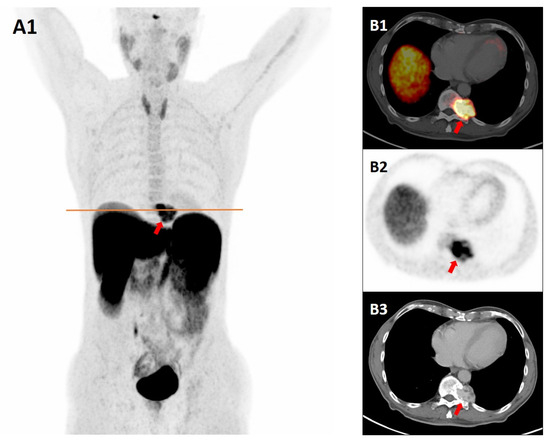

It is with great pleasure that I invite you to submit articles for the “Interesting images” Special Collection. Since we introduced Interesting Images as an article type in Diagnostics, it has served as a valuable resource for the imaging community. Many have relayed that they use these image-based case reports when encountering challenging cases or images of diseases rarely seen. Further, pitfalls are covered by this type of article and may be helpful both for experienced and less experienced image readers in making a correct evaluation.

The interesting Images together serve as a live imaging atlas covering PET, CT, MRI, and other imaging modalities. Therefore, the more cases we publish, the more likely it is that image interpreters with a difficult case can be supported by previously published cases. Although focus until now has largely been on clinical cases, it should be noted that nonclinical cases are also welcome, e.g., from preclinical in vivo imaging, including optical imaging as well as histology images from pathology.